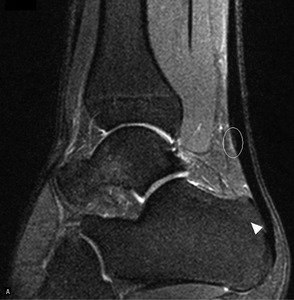

Pacjent, lat 52, zgłosił się do lekarza ortopedy z powodu silnego bólu w okolicy prawej pięty, który wystąpił nagle poprzedniego dnia podczas treningu piłki nożnej. Pacjent uprawia sport regularnie. Do tej pory nie cierpiał z powodu żadnych dolegliwości bólowych tej okolicy, a początek bólu nie był związany z bezpośrednim urazem. Podczas badania stopy okolica ścięgna Achillesa (piętowego) była obrzęknięta i bolesna, ruchy czynne w stawie skokowym znacznie ograniczone. Stwierdzono brak palpacyjnej bolesności w okolicy kostki przyśrodkowej i bocznej z zachowaną stabilnością w ruchach na boki.

Obrzęknięta okolica ścięgna Achillesa wraz z nagłym początkiem dolegliwości wskazuje na jego zerwanie. Niemniej możliwość wykonywania czynnych ruchów w stawie skokowym, nawet w niewielkim zakresie, przemawia za innym rozpoznaniem. Nie występuje też wyczuwalna luka w ścięgnie, jednak może być ona maskowana obrzękiem tej okolicy. Zapalenie kaletki głębokiej ścięgna Achillesa również może wywołać podobne objawy. Często wiąże się ono z występowaniem wyrośli kostnej na kości piętowej (deformacja Haglunda), która drażniąc kaletkę, wywołuje jej stan zapalny. Do złamań zmęczeniowych kości piętowej najczęściej dochodzi u żołnierzy oraz sportowców, którzy biegają długie dystanse po twardym podłożu. Jednakże w tym wypadku jest to mało prawdopodobne rozpoznanie, ponieważ pacjent może stanąć na pięcie oraz nie ma krwiaka i obrzęku tej okolicy.